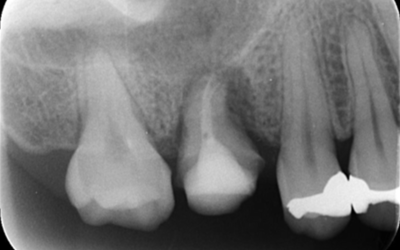

移植手術3ヶ月後のレントゲン画像

移植3ヶ月後。

歯根周囲に透過像を認めるが動揺などはなく、歯周ポケットも形成されていなかった。

移植12ヶ月後のレントゲン

移植12ヶ月後。セラミッククラウンで歯冠を修復した。

デンタルX線写真では透過像もほぼ消失している。